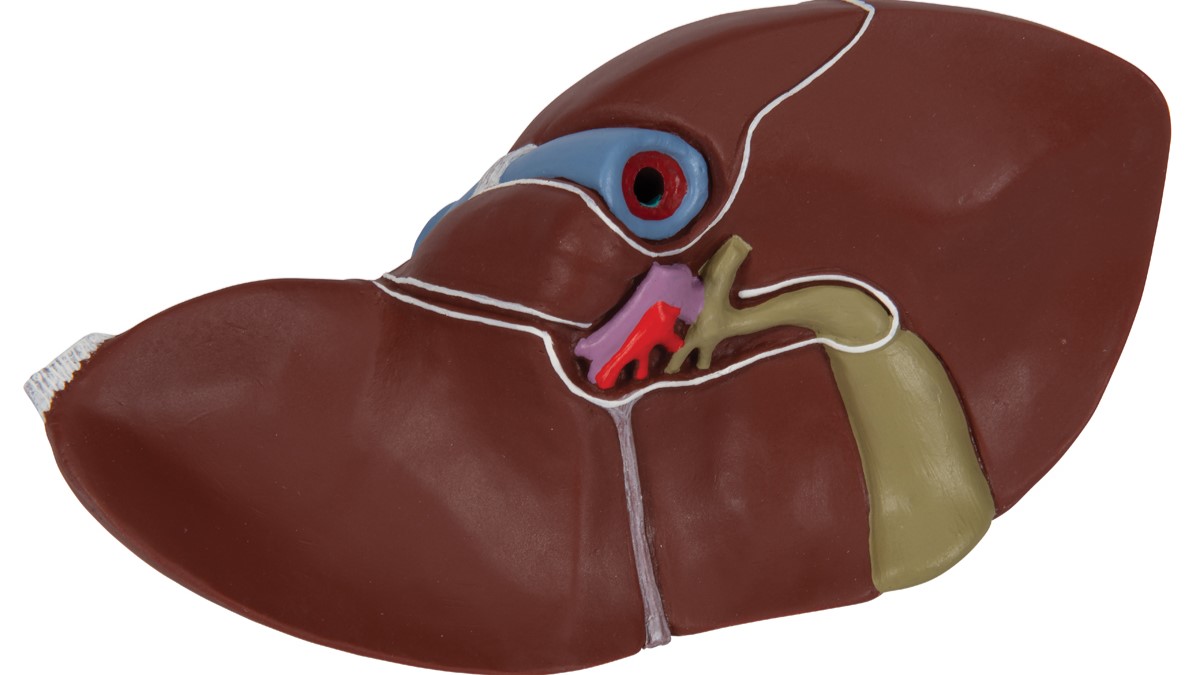

This realistic model shows the anatomy of the liver and gall bladder. The Liver with gall bladder shows:

4 lobes with gall bladder

Extrahepatic ducts

Hilus vessels

- Shows: 4 lobes with gall bladder, Extrahepatic ducts, Hilus vessels

Liver and Gall bladder properties featured:

- Liver

- Right lobe of liver

- Left lobe of liver

- Quadrate lobe

- Caudate lobe

- Proper hepatic artery

- Hepatic portal vein

- Common hepatic duct

- Neck of gallbladder

- Gallbladder